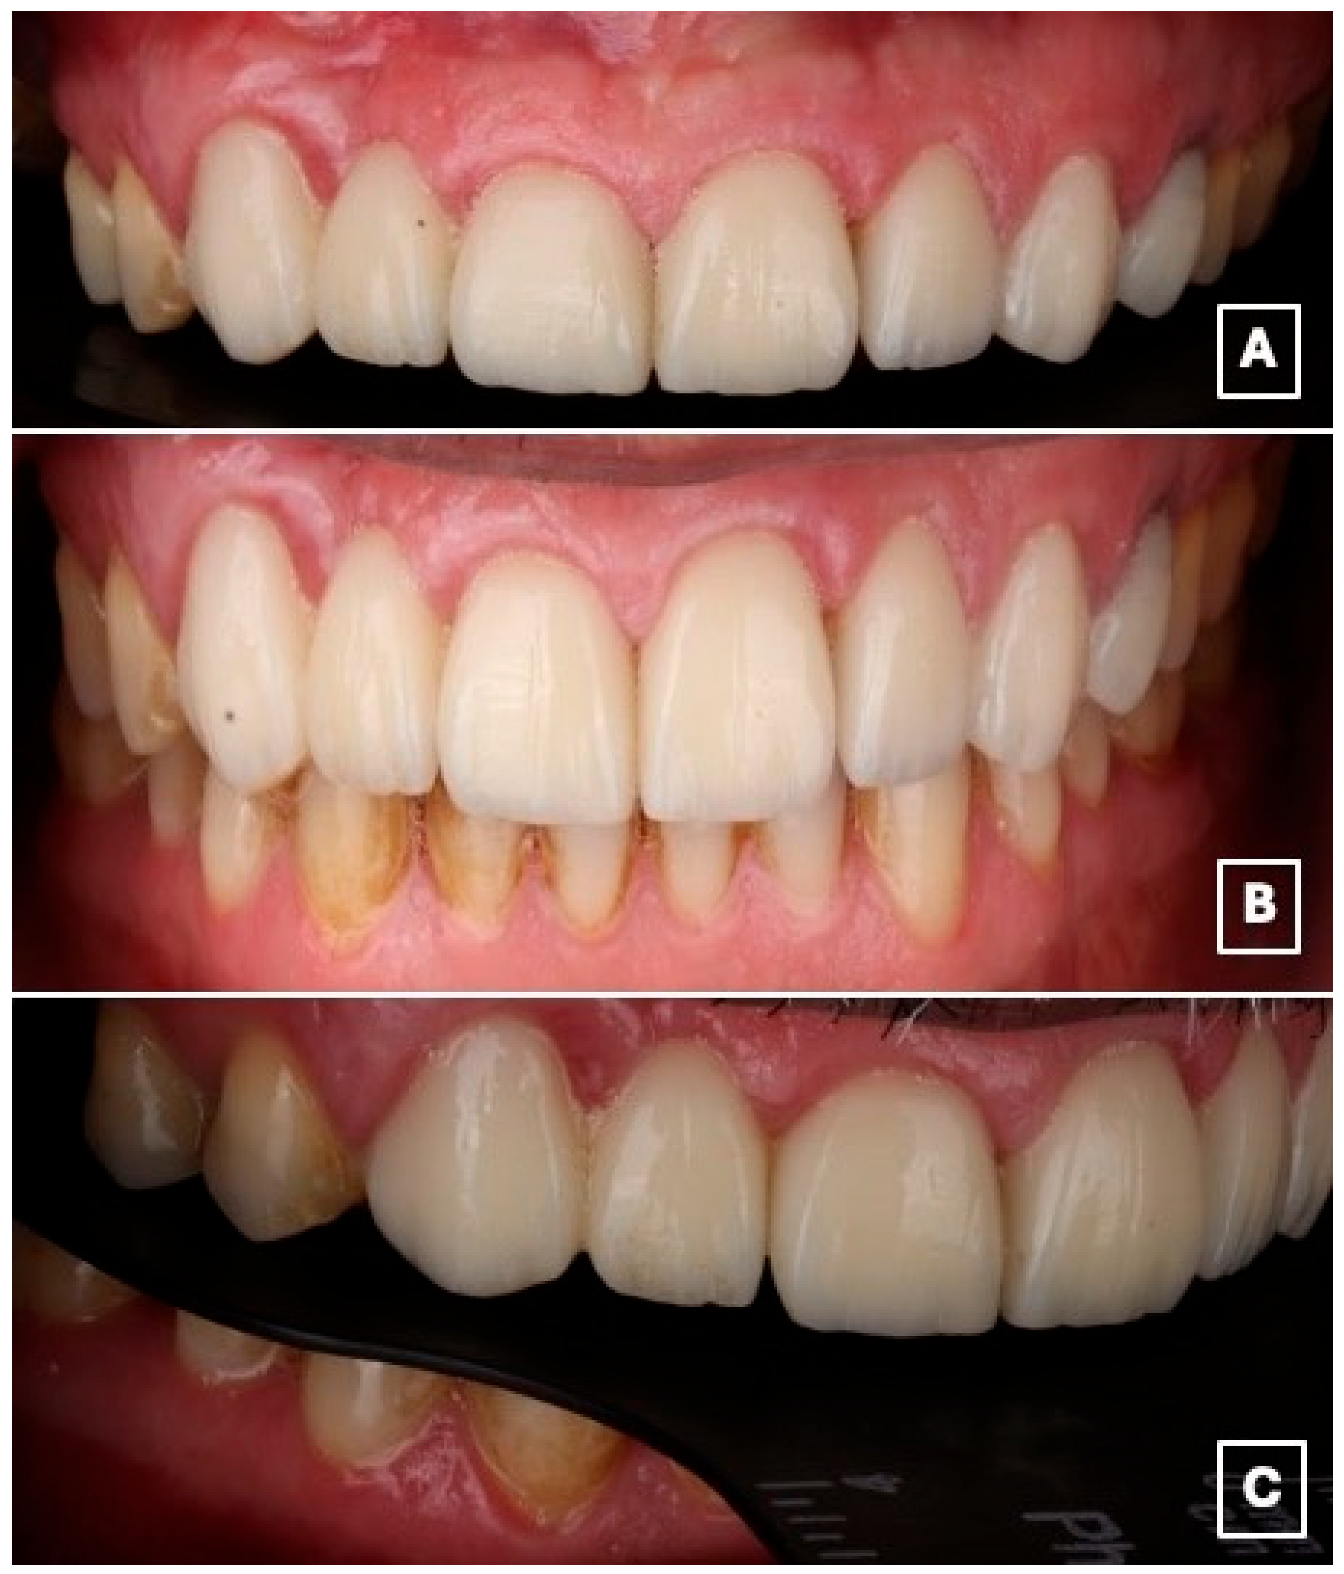

The patient reported satisfaction with the esthetic and functional outcomes of the treatment. Follow-up evaluations at 1 week, 1 month, 6 months, 1 year, and 18 months showed maintained adhesive retention, healthy peri-abutment soft tissues, and no evidence of technical or biological complications during the observation period (Figure 8A–C).

Figure 8.

Intraoral views at the 18-month follow-up demonstrate clinical stability of the restoration. (A) Frontal intraoral view showing stable esthetic integration of the cantilever RBFDP and laminate veneers within the smile. (B) Close-up frontal view highlighting maintained color stability, intact adhesive margins, and healthy peri-gingival tissues, suggesting favorable short- to medium-term adhesive performance. (C) Lateral intraoral view illustrating functional integration and preservation of occlusal relationships, with no evidence of chipping, debonding, or excessive wear at the cantilever region.